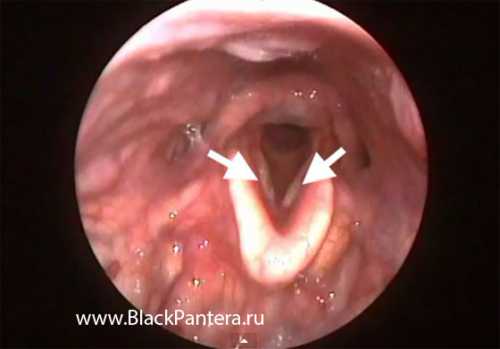

Под складочный ларингит возникает у детей дошкольного возраста. Заболевание характеризуется воспалением дыхательных путей, насморком, повышается температура тела, появляется кашель. Днем состояние удовлетворительное, дети чувствуют себя хорошо. А ночью приступ кашля усиливается, кашель носит лающий характер, возникает приступ удушья. Такое состояние недлительное протекает в течение получаса, затем появляется обильное потоотделение и ребенок засыпает. Такие приступы могут повторяться через несколько дней. При ларингос копии можно увидеть припухлость, она имеет симметричную структуру в виде валика. Под складочный ларингит возникает у детей дошкольного возраста. Заболевание характеризуется воспалением дыхательных путей, насморком, повышается температура тела, появляется кашель. Флегмонозный ларингит. Флегмонозный ларингит это гнойная форма острого ларингита.

Пациенты ощущают сухость во рту, им кажется, что в гортани находится какое то инородное тело. Голос быстро устает, после не длительного общения появляется охриплость. При ларингос копии отмечается застойная гиперемия слизистой. Можно обнаружить слизь в просвете гортани. Характеризуется хронической гиперплазией слизистой оболочки гортани. Бывает ограниченный и диффузный. Основной жалобой ларингита является охриплость голоса, может возникнуть даже его отсутствие. В период обострения заболевания признаки такие же как у катарального ларингита. Можно наблюдать симметричные выступы на голосовых связках. При ларингос копии наблюдается гипертрофия слизистой, можно обнаружить симметричные выступы. Он связан с недоразвитием слизистой оболочки носоглотки, иногда может возникать после перенесенной скарлатины или дифтерии.